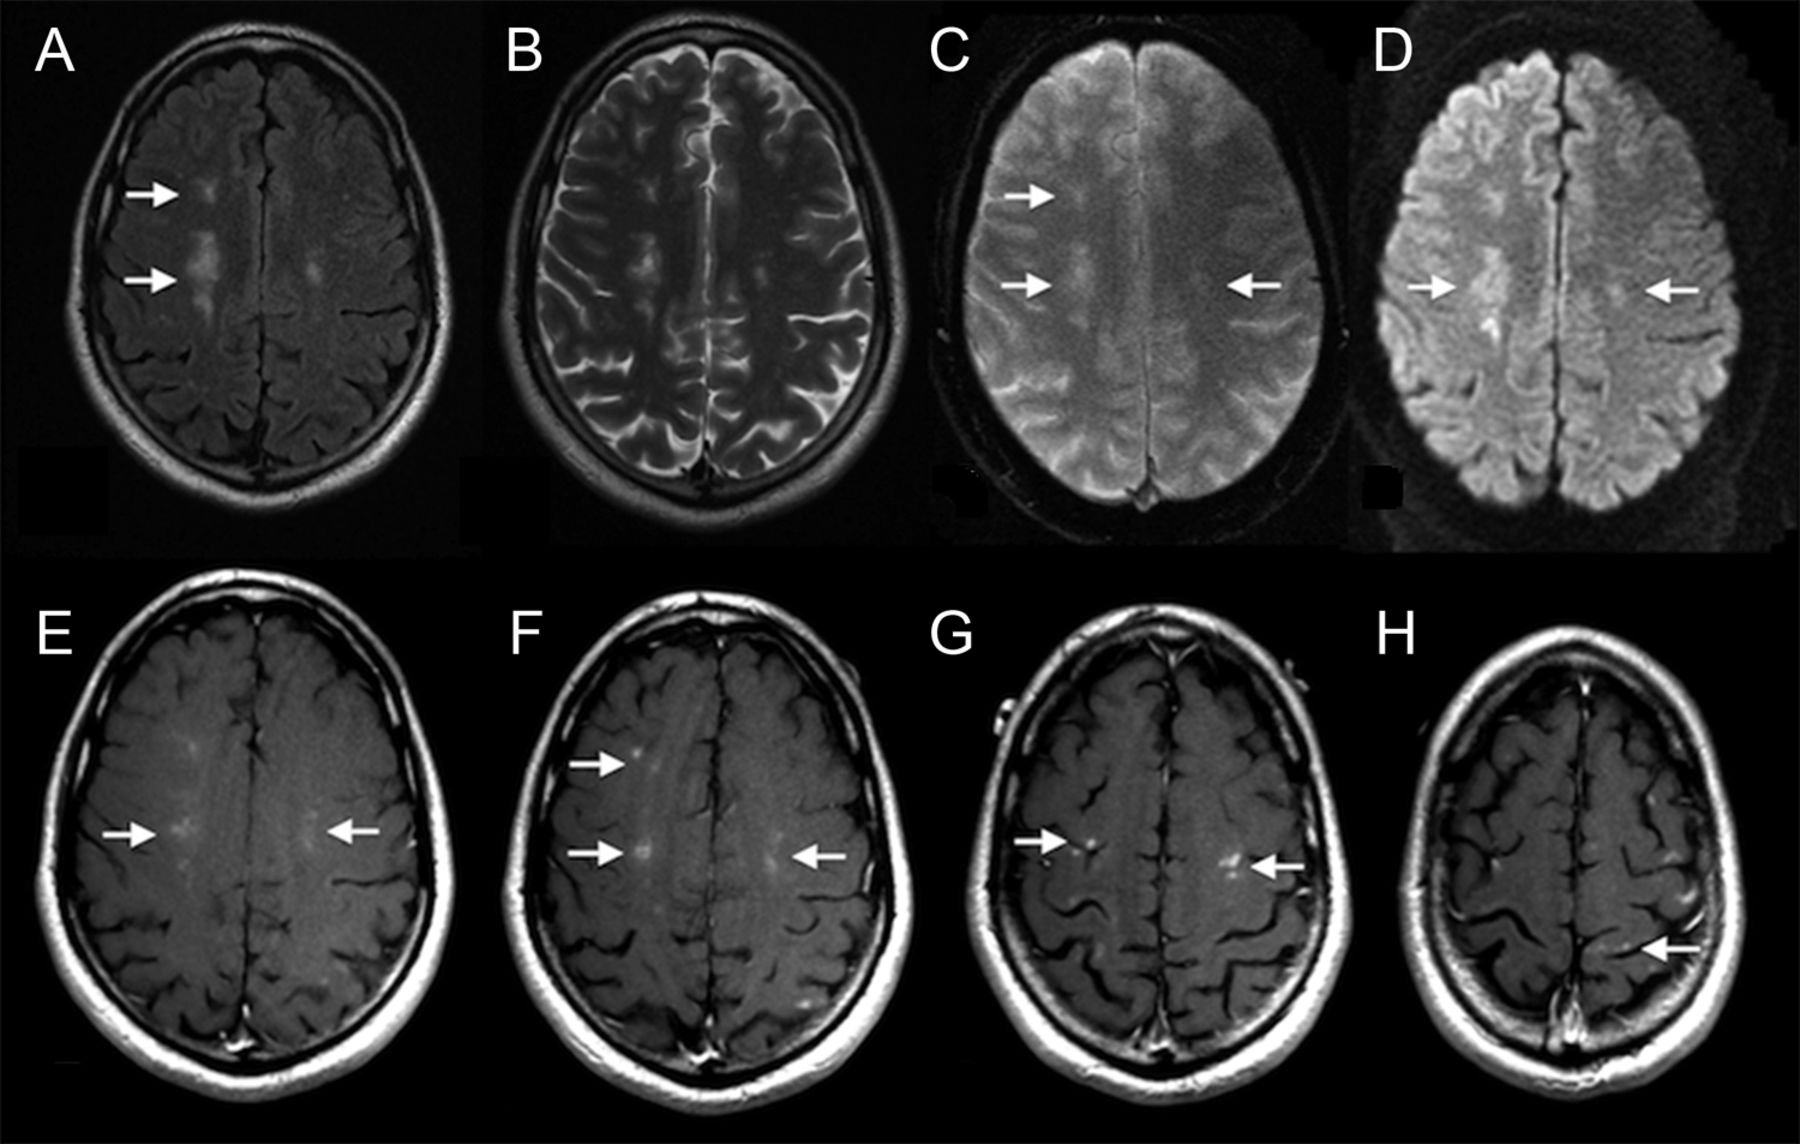

脑磁共振成像(图)展示了多个双边领域增加信号强度在深白质和灰白色物质界面的额叶和顶叶双边,用很少的病变在枕叶和颞叶和小脑T2 fluid-attenuated反转恢复(天赋)和T2加权扫描。Diffusion-weighted扫描证明限制在一些深白质病变,说明缺血。病变略hypointense unenhanced T1影像和没有病理盛开的工件在T2梯度回波序列,建议血液制品。对比政府后,有一个强烈的边缘增强在大多数病变。增强的面积小于4毫米在所有病变,T2和天赋信号异常病变周围测量8毫米。

多通道磁共振包括T2 fluid-attenuated反转恢复序列(天赋)三(一)T2涡轮旋转回声序列(B), T2梯度回波序列(C),和diffusion-weighted成像扫描(D),以及对比度增强t1序列(情况),展示多个分散,nonconfluent疫源地的T2和天赋hyperintensity深层白质(箭头)。没有异常的盛开的T2梯度回波序列,但限制扩散中看到一些病变。对比度增强可视化在深白质和多个皮质/皮质下区域。图像得到约7周在病人的疾病。